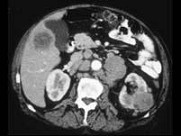

- 多项选择题男,54岁, 左侧腰痛,伴间歇性血尿2个月余, 结合所示图像,下列哪项描述正确 ( )

A、左侧肾癌

B、肝内多发转移癌

C、肝癌

D、左肾转移癌

E、腹主动脉旁及左肾门区淋巴结转移